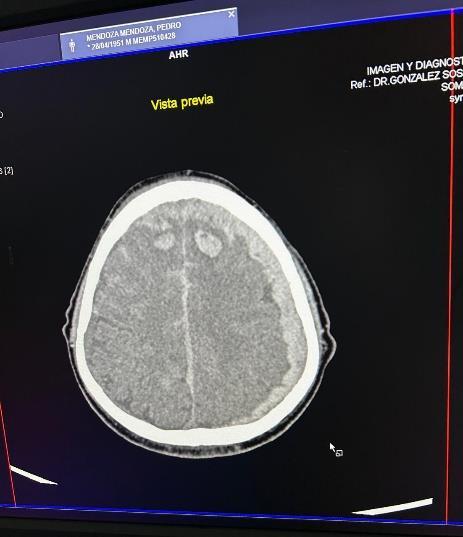

El cuadro clínico puede simular cualquier entidad neuroquirúrgica, es necesariocomplementarconundiagnósticoa través de la TAC de cráneo, que servirá no solo para confirmar el diagnóstico, sino para conocer su localización, volumen, compresión al parénquima cerebral y tiempo de evolución. Esto último es relevante a la hora de escoger el abordaje para el paciente, ya que un hematoma subdural que sea de inicioagudoseveráhiperdenso(70-90HU)y aquel que sea subagudo seráisodenso(28-48 HU). Estos son los más complicados de identificar, por su similitud con el parénquima cerebral. Finalmente, los HSDC seránhipodensos(Gómez,2021)

Los porcentajes relativos a los hallazgos del hematoma subdural el cual representa una masa hiperdensa en forma de semiluna (100%) (Figura 2) con un borde lateral y medial establecido de convexo y cóncavo respectivamente, la que se asocia a

una lesión cefálica la cual se asocia en su mayoría a accidentes de tránsito (70%) (Patiño,2024).

2.

PresentaciónclásicadelHematomasubduralenforma“Semiluna”

Nota: La siguiente imagen propia del autor.

Los HSDC se clasifican de acuerdo con: las estructuras internas, extensión intracraneal y densidad mostrada en tomografías computarizadas o resonancias magnéticas;yaque estospatronesgraduados detallados ayudan a predecir el riesgo de recurrencia del hematoma, especialmente en pacientes susceptibles al proceso preoperatorio, el tratamiento es necesario para reducir la recurrencia postoperatoria u otras complicaciones quirúrgicas. (Parra, 2023)

Los hematomas suelen ser hipodensos (Figura 3), pero también se observan lesiones isodensas o de densidad mixta. Aunque estos suelen ser cóncavosconvexos,raravezpuedenimitarhematomas epidurales agudos. Los HDSC isodensos bilaterales puede causar dificultades considerables en el diagnóstico por tomografía computarizada. La resonancia magnética nuclear podría ayudar a hacer el diagnóstico de tales lesiones. (Fuenmayor, 2020)

Figura

Figura 3.

Presentación clásica del Hematoma subdural crónico hipodenso.